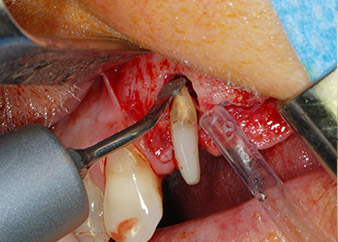

Then the apex was abraded with the same instrument to remove residual infected apical tissue and to reduce possible accessory root-canal ramifications (apicoectomy) (Fig. 5). A retrograde filling was not necessary because the orthograde filling had just been revised.

buccal apex of tooth 24

Fig 5: ... and the buccal apex of tooth 24 was abraded with the same instrument (apicoectomy).

Prior to implant placement, infected tissue was removed from the alveolar bone in the implant site and around the abutment teeth with an insert originally designed for bone shaping and collecting bone chips (Piezomed, insert B5) (Figs. 6 and 7).